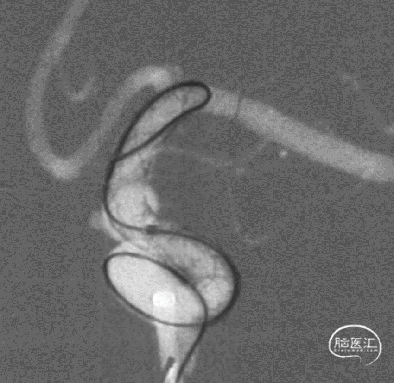

3、释放TB Plus过程中,头端铆钉效果满意,释放过程顺滑。

4、通过微导丝按摩,可以使TB Plus贴壁效果更加。

5、FD植入后,动脉瘤明显造影剂瘀滞,效果显著。

6、Tubridge Plus材料改进后通体显影,可以更好观察支架的贴壁性及术中打开情况,提高释放安全性。